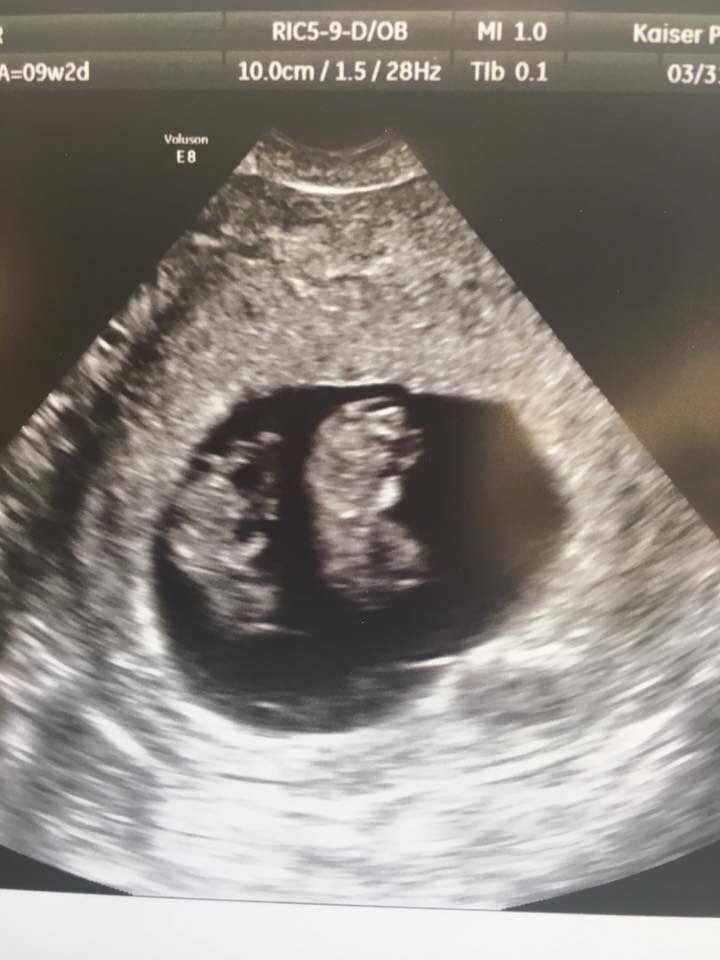

On March 7 at my post operation obstetrics appointment, I found out that my child split into identical twins. There were two tiny sacs with two blipping heartbeats on the ultrasound monitor. In an instant, I knew I wanted these children. They were a miracle I was given, and I would fight for them. My boyfriend and I celebrated moments of connection between his manic moments of verbal abuse and constant control.

Just before the second trimester, around week 11, I went in for the Nuchal translucency exam. The ultrasound technician was friendly and talkative, until suddenly, he wasn’t. He excused himself to get my doctor, even though my appointment with her was in a few hours.

Abortion is a procedure outside of a pro-life or pro-choice debate. There is no other word for my experience. As I was looking for an image for this post, it was hard to find one that doesn’t violently attach a choice to the procedure. I’m using my own pictures, instead. This is all I have to remember them by. Legislation is unclear on medical practices because most politicians don’t actually practice medicine. Belief rallies are speaking in riddles that won’t address the topic. You don’t know what someone is facing until they’ve shared it with you. A procedure has little to do with the decision around bringing life into the world.